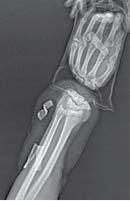

Masculino de 37 años de edad que el día 11/02/2019 recibió agresión por terceras personas con objeto corto contundente, lo que condiciona amputación de mano izquierda, a nivel del carpo (Figuras 1 a 3). La mano es puesta en condiciones apropiadas en un medio húmedo y térmico y el paciente es estabilizado hemodinámicamente en el Servicio de Urgencias. Se realiza el procedimiento con dos equipos quirúrgicos, uno trabajando con la mano y el otro con la extremidad afectada: se realiza un aseo de la extremidad superior izquierda, se inicia con estabilización ósea, posteriormente con la reparación término terminal de la arteria radial y cubital en compañía de sus dos venas respectivamente, se realiza neurorrafia de nervio radial y cubital, se continúa con tenorrafia de tendones flexores y extensores, se retira la isquemia y se corrobora que no haya hemorragia activa; posterior a cuatro horas de evolución se realiza reimplante de mano en cinco horas de procedimiento quirúrgico. No se requirió manejo en Unidad de Cuidados Intensivos, ya que el paciente se encontraba estable (Figuras 4 y 5). Posterior a seis meses, después de seguimiento y tratamiento de rehabilitación, se recupera aproximadamente 70% de la función de la mano, logrando pinzas gruesa y fina funcionales, las cuales le permiten tomar objetos pequeños como un bolígrafo.

Figura 1

Figura 2

Figura 3

Figura 4

Figura 5